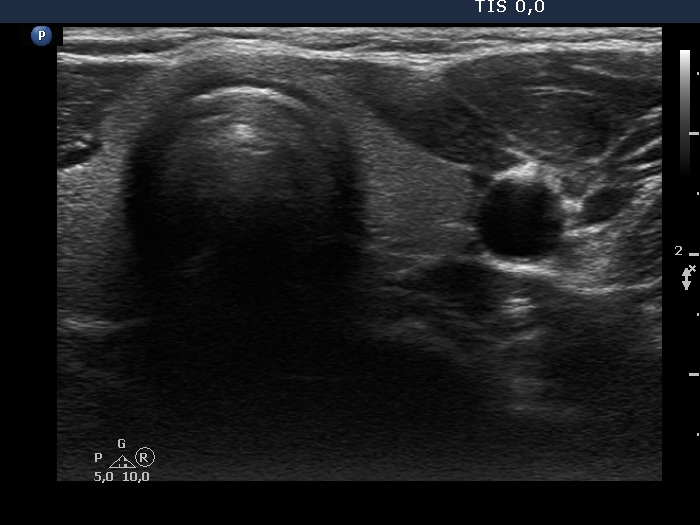

Teamwork - case 894 (ultrasonographic picture 8)

Left lobe, transverse scan. This lobe is intact.